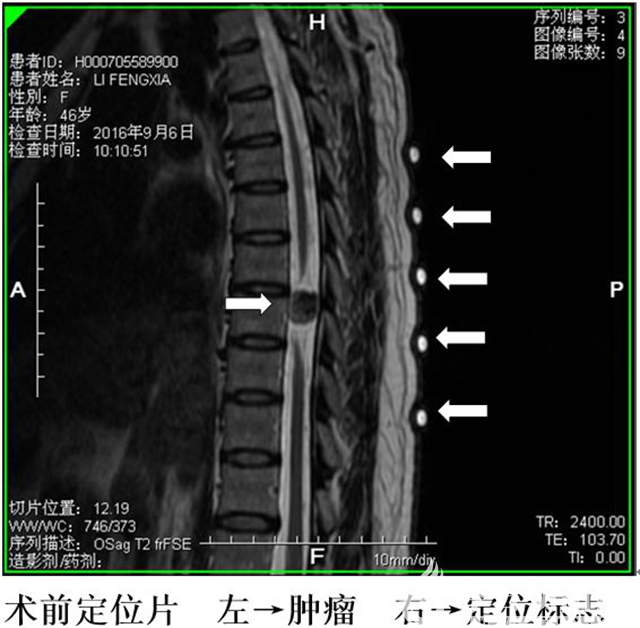

神經(jīng)外二科組織會(huì)診,根據(jù)患者病變性質(zhì)、癥狀進(jìn)行性加重、中胸段病變?nèi)狈Χㄎ粯?biāo)志等情況,決定為其實(shí)施精準(zhǔn)定位手術(shù)。術(shù)后,患者下肢肌力恢復(fù)正常,肋弓以下感覺(jué)明顯恢復(fù),出院時(shí)患者可下地行走,患者及家屬非常滿意。

據(jù)介紹,頸椎和腰椎手術(shù)可根據(jù)體表定位標(biāo)志定位,也可術(shù)中暴露棘突后辨認(rèn)形態(tài)定位,胸椎棘突呈疊瓦狀排列,形態(tài)上無(wú)顯著差別,尤其中胸段(胸5-8)病變處于前不著村后不著店?duì)顟B(tài),術(shù)前定位難度大,精準(zhǔn)定位更難,易出現(xiàn)定位不準(zhǔn),增加手術(shù)難度和復(fù)雜程度,對(duì)于肥胖患者更是難以捫清棘突,傳統(tǒng)方法如用曲別針拍X光片定位也會(huì)在擺體位變化移位,臨床上中胸段多有開錯(cuò)節(jié)段的報(bào)道。